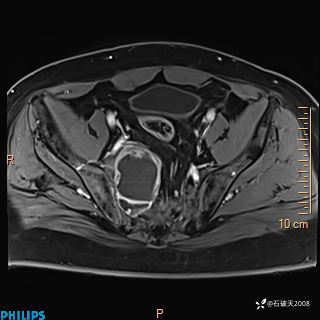

现病史:7个月前患者因骶尾部占位就诊于北京大学人民医院,MRI示:骶骨右侧及右骶前占位,考虑骨巨细胞瘤可能,动脉瘤样骨囊肿可能,神经源性肿瘤待排。行手术治疗,术后病理回示:XXXXX。术后给予对症治疗,具体不详,恢复良好。近几个月反复出现发热,伴骶尾部不适,多次住院给予对症治疗,2天前患者无明显诱因再次发热伴骶尾部不适,无大小便失禁,为求进一步治疗,遂门诊来我院,在门诊初步检查后,以“骶尾部肿物”为诊断收入我科。入院来患者神志清,精神一般,饮食睡眠可,大小便无明显异常,体重无下降。

2023年3月份MRI影像

增强轴位